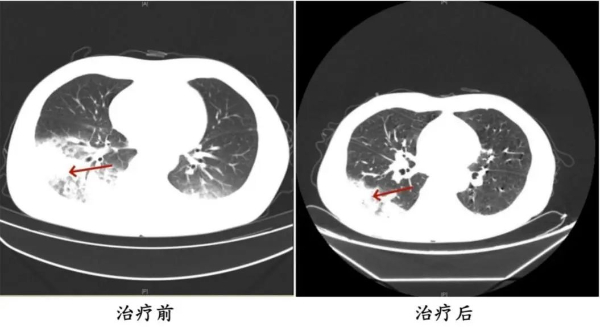

周先生治疗前后的肺部CT影像

医生判断患者有可能感染了军团菌,建议患者完善纤支镜检查,留取肺泡灌洗液标本查找病原体。最终,患者肺泡灌洗液NGS(Next-Generation Sequencing,下一代测序)检测结果显示:嗜肺军团菌,明确诊断为军团菌肺炎。医生马上调整治疗方案,改用可覆盖嗜肺军团菌的一线用药抗感染,患者体温逐渐下降,次日体温恢复正常,经过后续治疗康复出院。